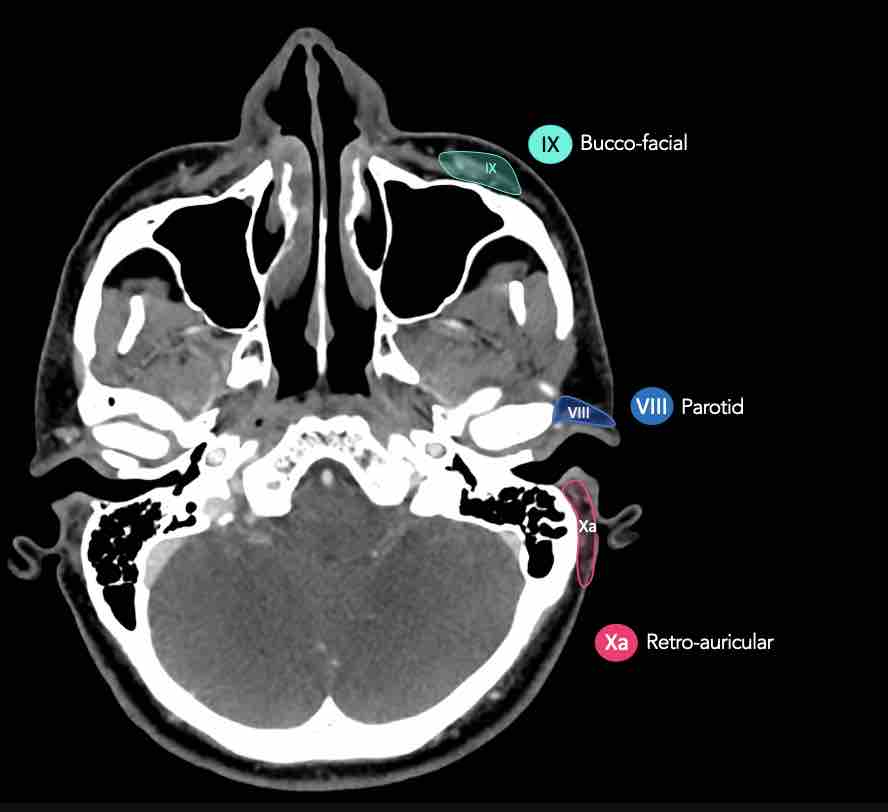

CT Scan Mặt Cắt Ngang (Axial CT)

Các lát cắt CT mặt phẳng ngang tương ứng với hình minh họa tổng quan.

Các lát cắt CT mặt phẳng ngang với hình ảnh chi tiết hơn.